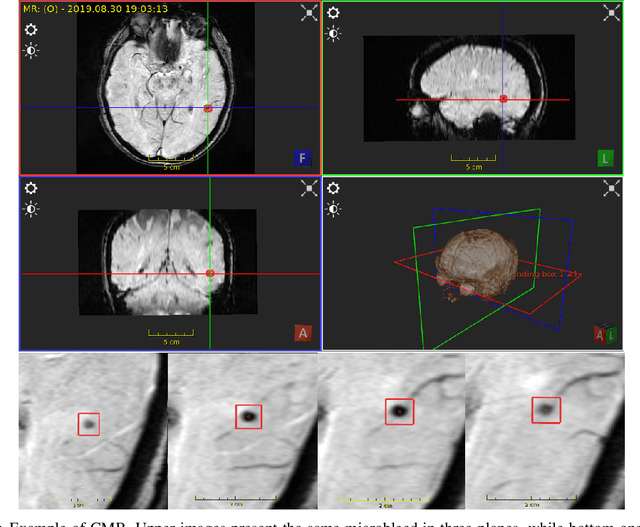

Abstract:Cerebral microbleeds detection is an important and challenging task. With the gaining popularity of the MRI, the ability to detect cerebral microbleeds also raises. Unfortunately, for radiologists, it is a time-consuming and laborious procedure. For this reason, various solutions to automate this process have been proposed for several years, but none of them is currently used in medical practice. In this context, the need to systematize the existing knowledge and best practices has been recognized as a factor facilitating the imminent synthesis of a real CMBs detection system practically applicable in medicine. To the best of our knowledge, all available publications regarding automatic cerebral microbleeds detection have been gathered, described, and assessed in this paper in order to distinguish the current research state and provide a starting point for future studies.